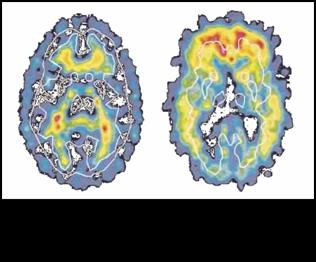

Tomografia ed

emissione di positroni: a sinistra il cervello di un malato di Alzheimer

con molte zone rese inattive dalle placche di amiloide; a destra un

cervello che manifesta i primi sintomi della malattia